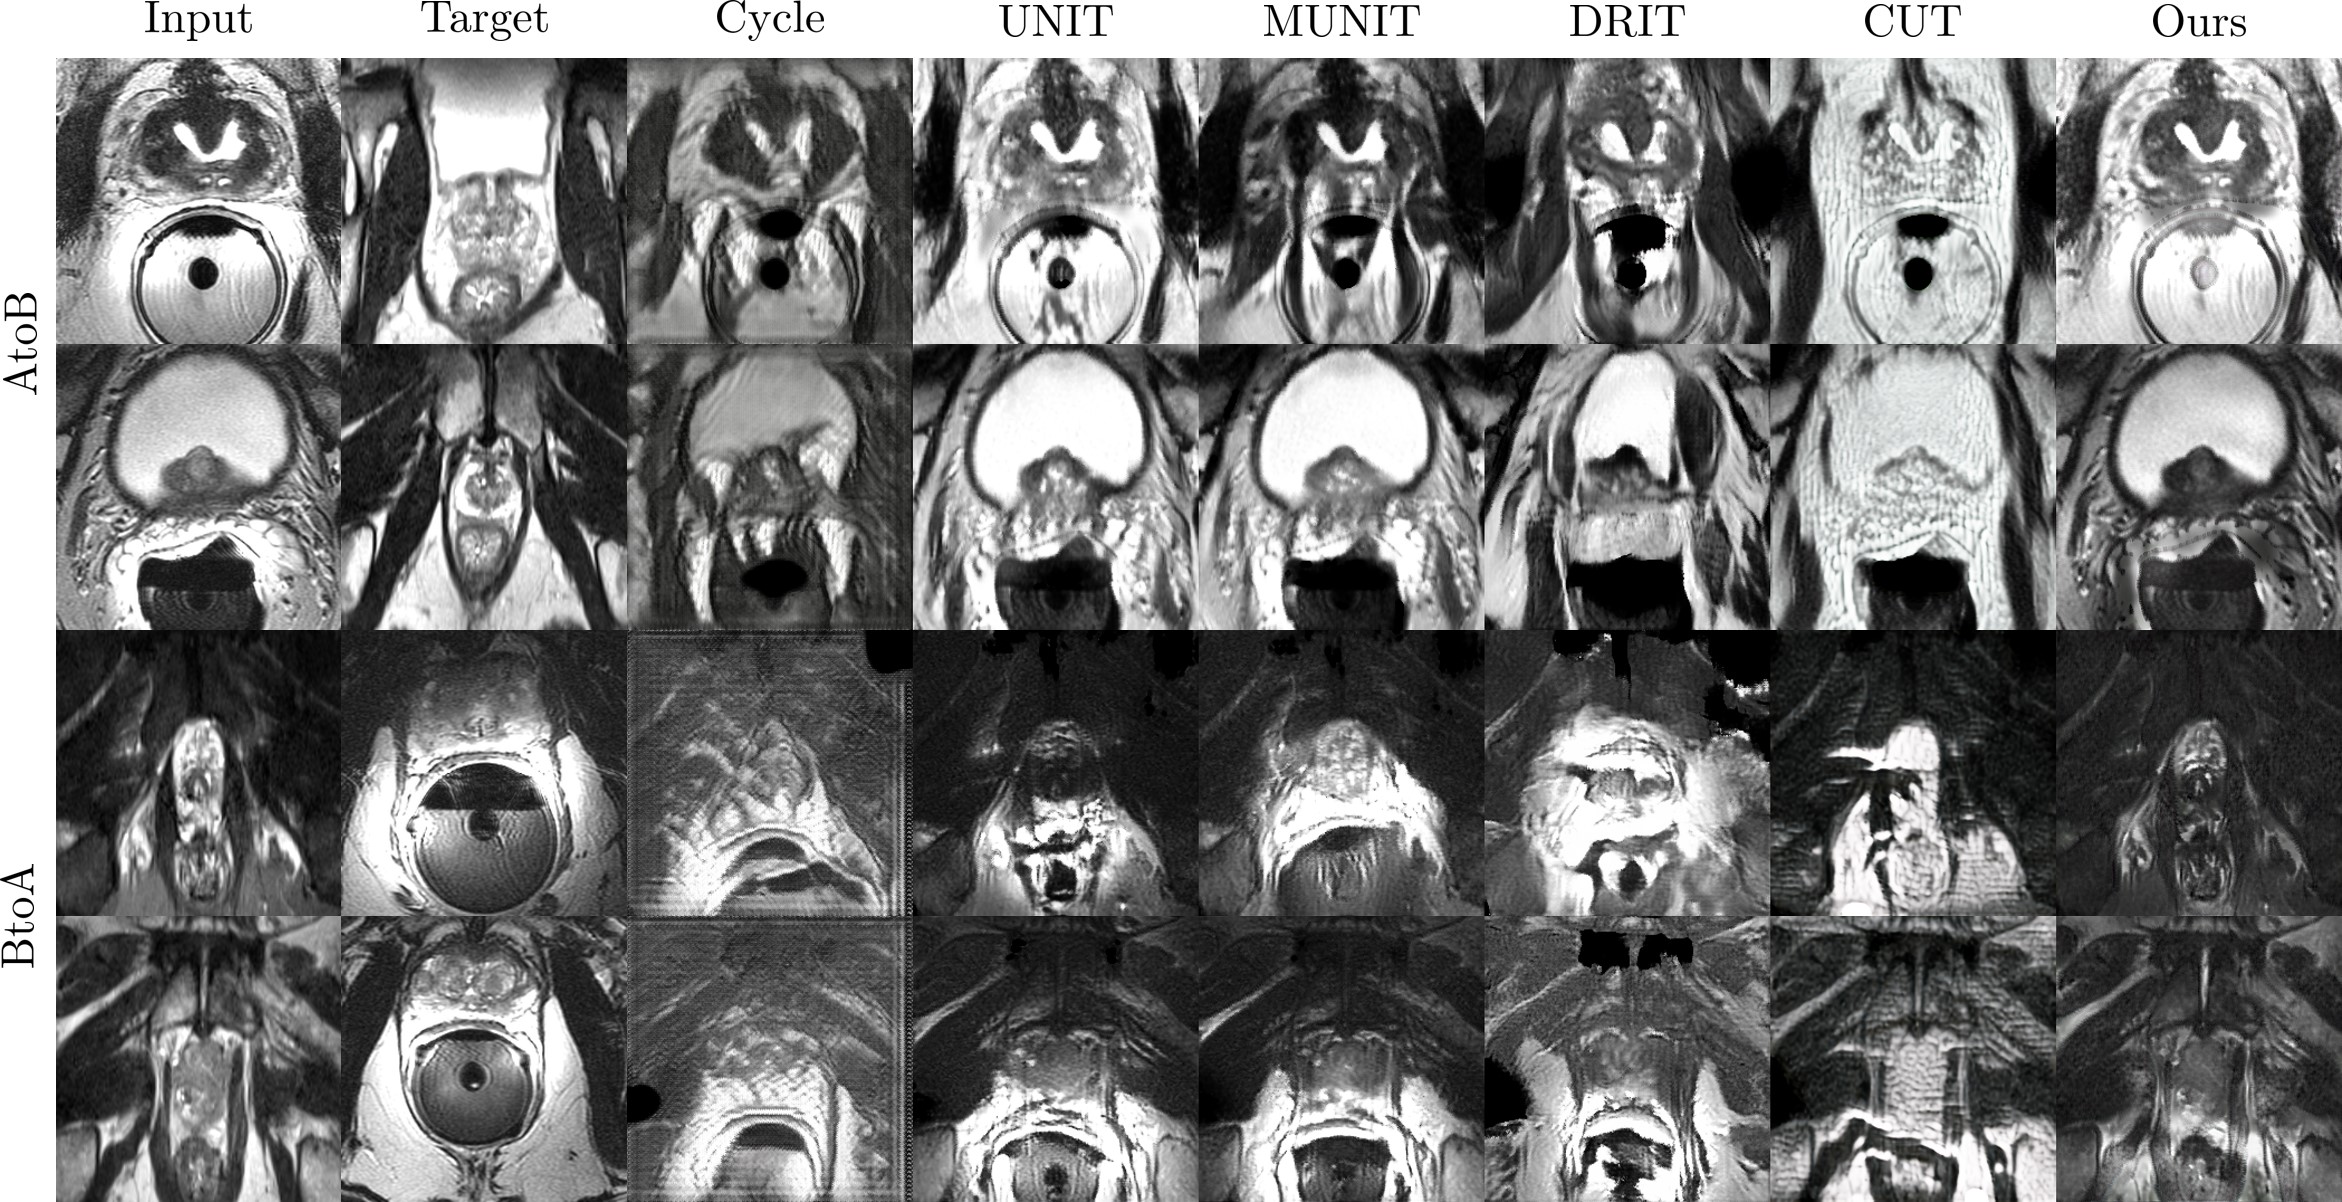

Refer to caption

Figure 11: Qualitative results of five image translation models and the proposed on the prostate dataset.

5.3.2 Prostate

We report the segmentation performance on prostate datasets in Table 4. To better highlight performance, we also present visual comparison on the quality of the generated images in Fig. 11. Overall, our method reports the best performance against existing methods. CycleGAN, DRIT, UNIT BtoA, and MUNIT showed extensive content distortions in the source image and while UNIT AtoB had relatively fewer content distortions with fewer texture updates. In addition, CUT translated images included artifacts (noise) and checkerboard patterns initially absent in the target image. Based on the reported quantitative (Table 4) and qualitative results (Fig. 11), we believe that the visual quality of the translated images is highly correlated to actual model performance. In contrast to prior approaches, our method shows high-quality image translation able to maintain the content of the source image while successfully transferring the texture of the target image using the proposed losses.